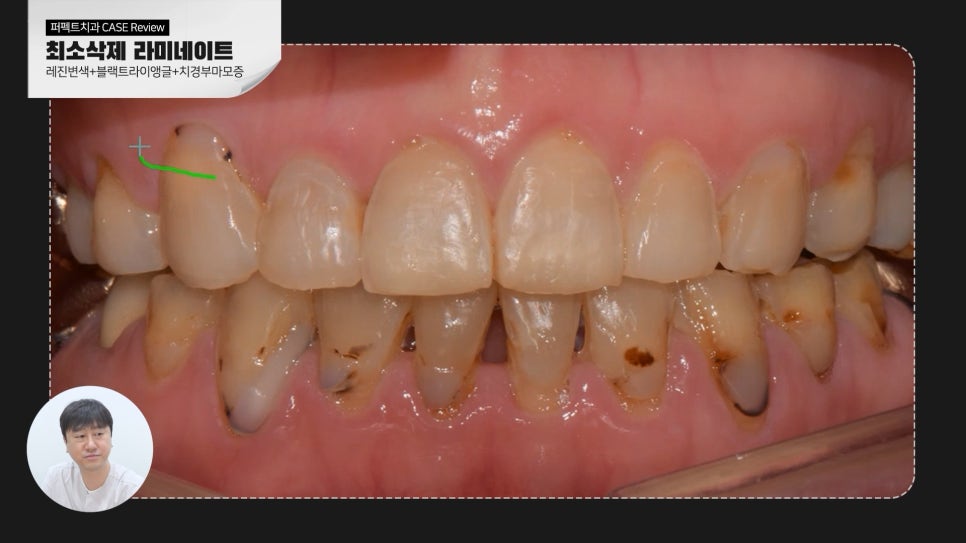

오늘은 변색된 레진을 최소삭제 라미네이트로 교체한 케이스에 대해 알아보겠습니다.

환자분께서는 더 심미적이고 하얗고 가지런한 치아를 원하셨고

블랙트라이앵글 즉 치아 사이의 틈을 메꿀 수 있길 바라셨습니다.

때문에 웃을 때 보이는 치아 8전치 치료를 진행하기로 하였습니다.

가지런하고 고른 치열을 가지고 계셨기 때문에 0.1mm 최소삭제로 진행했는데요.